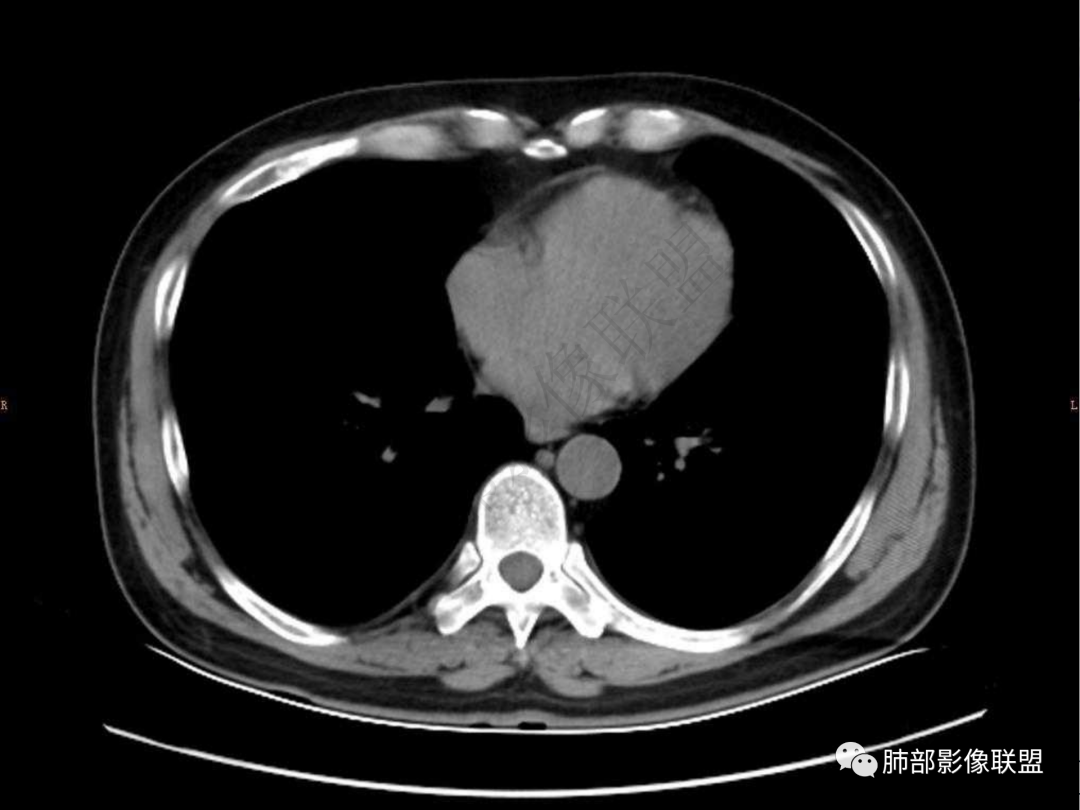

4.实性部分不均匀环形强化并显示一小范围低密度坏死区或空洞。较之肺窗,整体纵隔窗范围较小,提示病灶并不十分密实。抑或为不同时段图像。

肺脓肿:边界模糊不清,或者块影为类圆形,无明显分叶,边缘平直为主,刀切征——炎性特点三、病灶周围特点:肺脓肿:病灶非远端有片状GGO——炎性特点四、近端支气管阻塞:肺脓肿:常有引流支气管伴管壁增厚或者支气管沿洞壁走行。五:坏死壁:肺脓肿:大多壁厚,少数壁薄,没有壁结节,内壁清楚光整——炎性特点

六:增强扫描:

肺脓肿:环形强化,强化较显著。如出现明显囊壁样强化甚至边缘“憩室”样突出,高度支持肺脓肿。